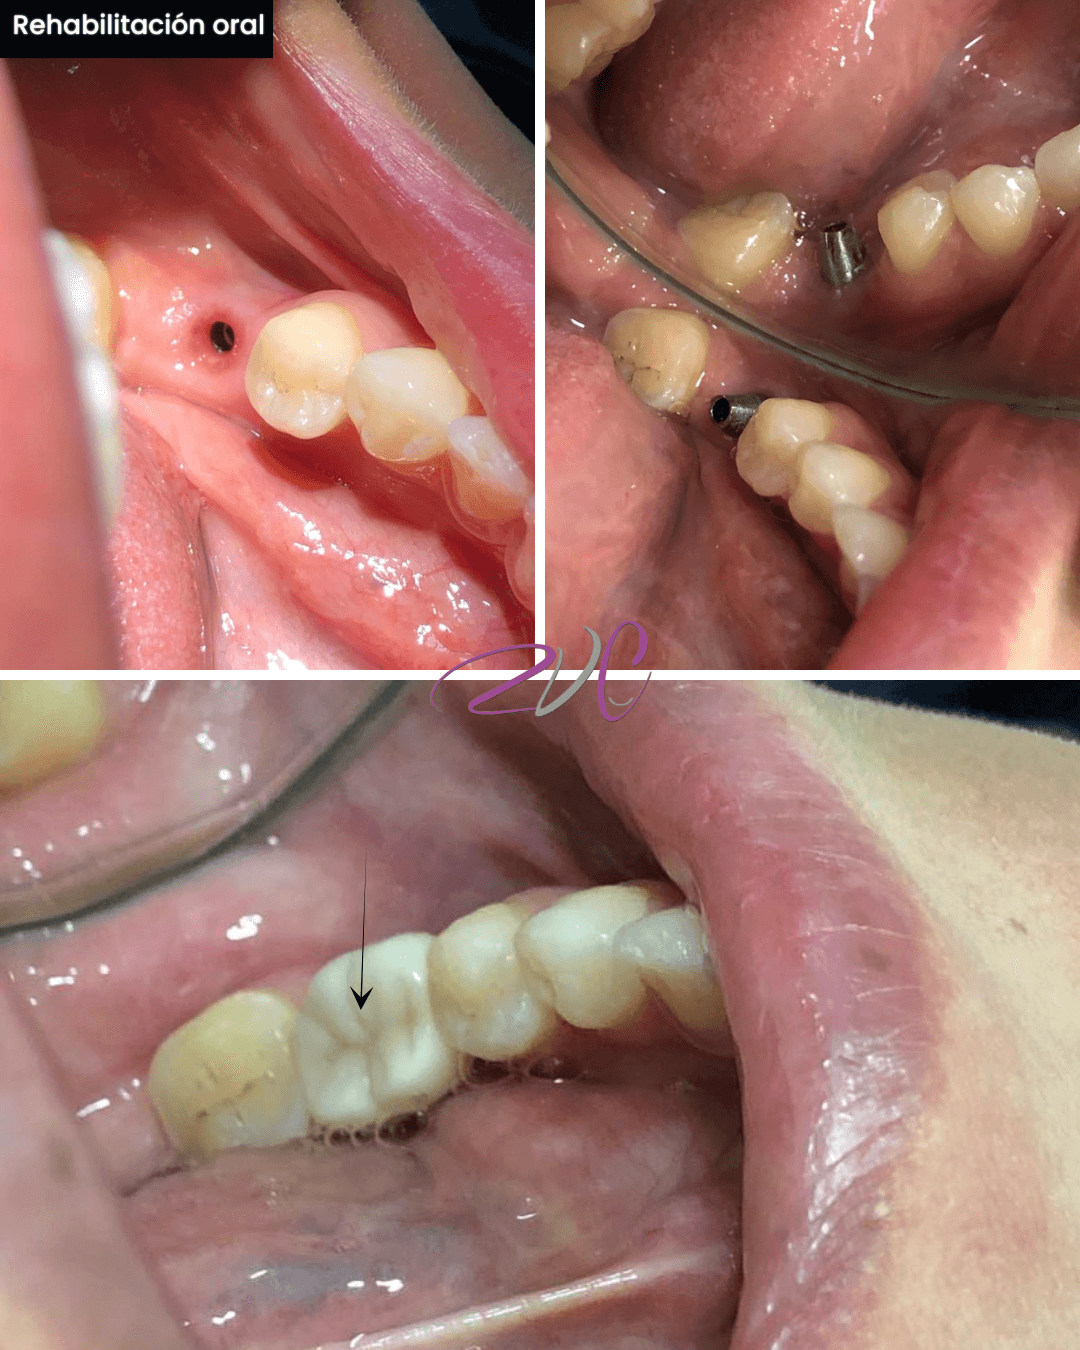

Rehabilitación Oral

Especialidad enfocada en restaurar la funcionalidad y estética de la boca cuando se han perdido dientes o estructuras dentales. Incluye tratamientos como coronas, puentes, prótesis fijas o removibles e implantes dentales. Ideal para devolver salud, estabilidad y confianza al paciente.